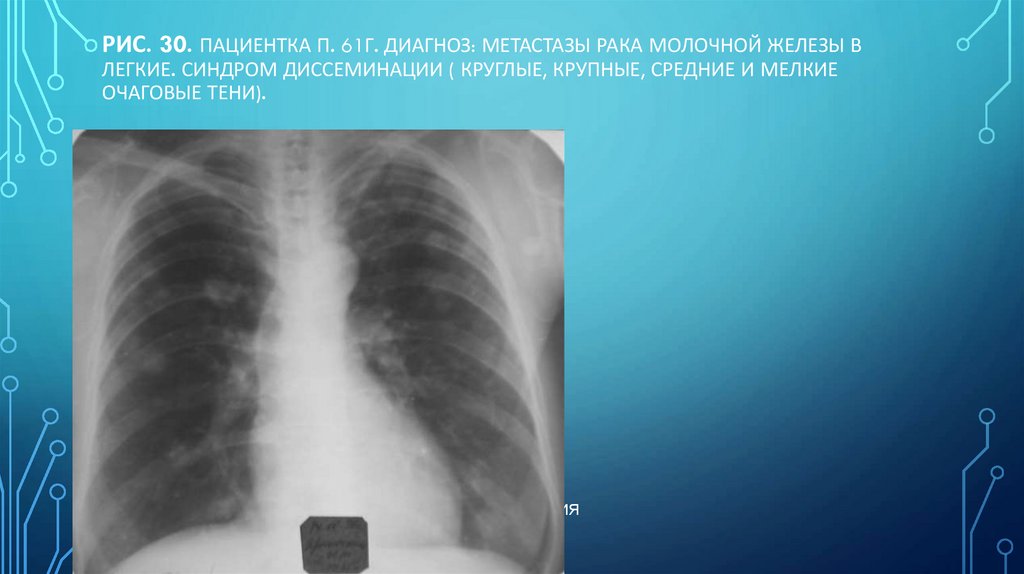

111. Рис. 30. Пациентка П. 61г. Диагноз: Метастазы рака молочной железы в легкие. Синдром диссеминации ( круглые, крупные, средние и

РИС. 30. ПАЦИЕНТКА П. 61Г. ДИАГНОЗ: МЕТАСТАЗЫ РАКА МОЛОЧНОЙ ЖЕЛЕЗЫ В

ЛЕГКИЕ. СИНДРОМ ДИССЕМИНАЦИИ ( КРУГЛЫЕ, КРУПНЫЕ, СРЕДНИЕ И МЕЛКИЕ

ОЧАГОВЫЕ ТЕНИ).

Н.С. ВОРОТЫНЦЕВА. С.С. ГОЛЬЕВ РЕНТГЕНОПУЛЬМОНОЛОГИЯ